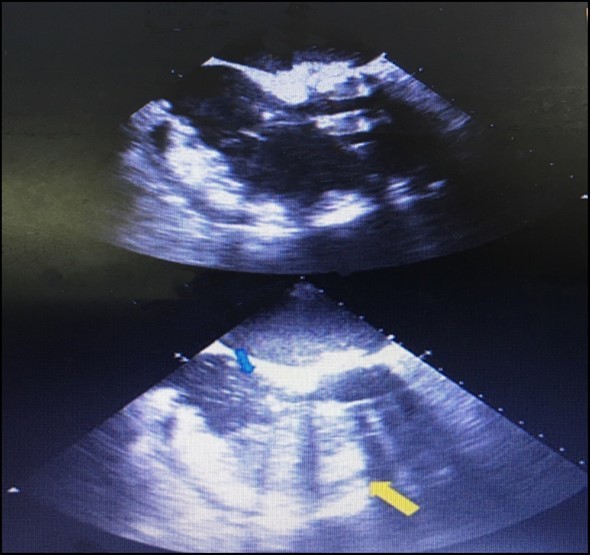

We describe a case in which an easy action, such as instillation of agitated saline, allowed us to confirm a major complication related to pericardiocentesis. A 62-year-old man with a history of mitral and aortic valve replacement 2 weeks earlier presented with complaints of dyspnea and asthenia. Laboratory tests and chest x-ray revealed the presence of massive right hemothorax and severe secondary anaemia. Despite blood transfusion and chest tube insertion, the patient’s hemodynamic situation continually worsened, and he finally developed cardiac arrest. During cardiopulmonary resuscitation, an urgent echocardiogram showed severe pericardial effusion. Therefore, pericardiocentesis by a subxiphoid approach was performed. After stabilisation, the patient was transferred immediately to coronary care unit. The pericardial tube had been left in place. Continuous blood drainage was noticed after shifting and agitated saline was injected through the drainage tube to define its precise location. Right ventricular opacification was observed during a repeat echocardiogram with massive bubbles confirming the drainage tube was placed actually within the right ventricle (Figure 1). This case emphasizes the importance of instillation of agitated saline as a supplementary technique while performing echo-guided pericardiocentesis in order to reduce the likelihood of cardiac chamber perforations. Subsequent sections will discuss more frequent complications of pericardiocentesis including rates, severity, and other important procedural and non-procedural considerations.

Figure 1.The complete opacification of the right ventricle (yellow arrow) and the presence of some bubbles within the right atrium (red arrow),denoting that the tip of the drainage tube is malpositioned within the right ventricle.